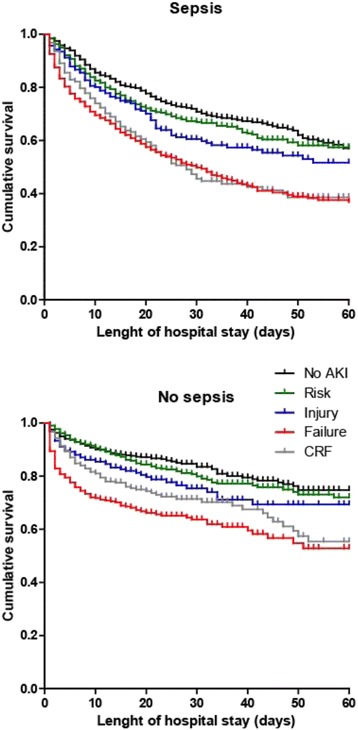

P201 - Time length below blood pressure thresholds and progression of acute kidney injury in critically ill patients with or without sepsis: a retrospective, exploratory cohort study